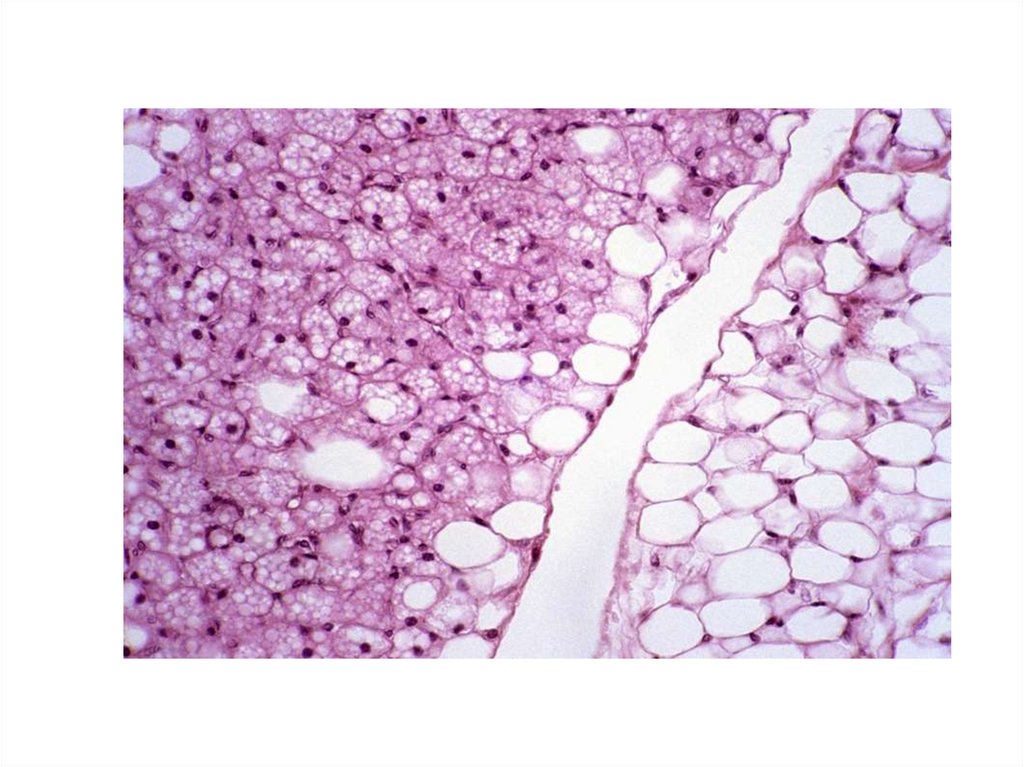

• Белая жировая ткань

• Развивается из

мезенхимы

• Состоит из долек,

разделенных тонкими

прослойками рыхлой

волокнистой

соединительной ткани,

несущие кровеносные

сосуды и нервы.

• Однокапельный

адипоцит, мало

митоходрий

• Локализация - под кожей,

в сальнике, брыжейке и

других жировых депо.

• Функции - депо воды,

энергии, жирорасворимых

витаминов, термоизоляция,

опорная

Жировая ткань обладает высокой метаболистической активностью, а

запасы ее липидов непрерывно динамично обновляются через

липогенез и липолиз. Жировая ткань у среднего человека содержит

80% энергетических запасов тела. Она обеспечивает примерно 40дневную потребность в энергии.

Жировая ткань вырабатывает гормоны адипокины – ключевые

регуляторы массы тела, воспаления, метаболизма глюкозы и др.

процессов. Поэтому ожирение ассоциируется в сахарным диабетом,

атеросклерозом, гипертонией и раком.

Адипоциты накапливают и вырабатывают женский половой гормон

эстроген.

Лептин (в 1994) - оказывает действие на уровне гипоталамуса,

вызывает ощущение сытости и снижает потребление пищи (подавляет

прием пищи).

Адипонектин – регулирует уровень глюкозы и расщепление жирных

кислот